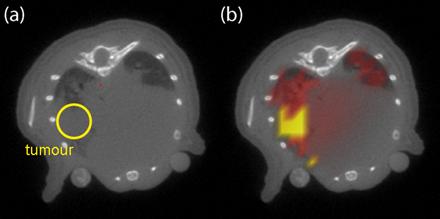

Bild für EU-Projekt 2B